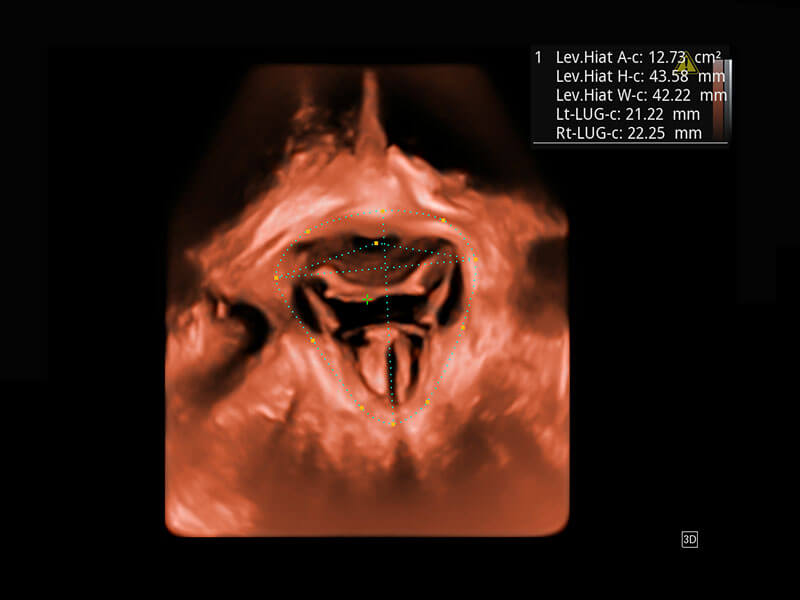

盆底超声

P60为盆底超声检查提供应用方案,多种腔内及腹部容积探头提供从二维、三维到四维的优异图像品质,实时快速三维容积数据获取,专业的测量工具包等人性化设计,为超声医生诊断提供有力保障。

Lev.Hiat A-r: 16.33 cm2

Lev.Hiat H-r: 53.70 mm

Lev.Hiat W-r: 43.96 mm

Lt-LUG-r: 24.16 mm

Rt-LUG-r: 19.94 mm

S-Pelvic

能够简化盆底检查的操作流程,可在二维模式及三维成像模式下实现一键自动提取出标准切面、自动识别当前切面、自动测量,提升盆底检查的高效性,同时也能让青年医生快捷的获得准确的检查结果。